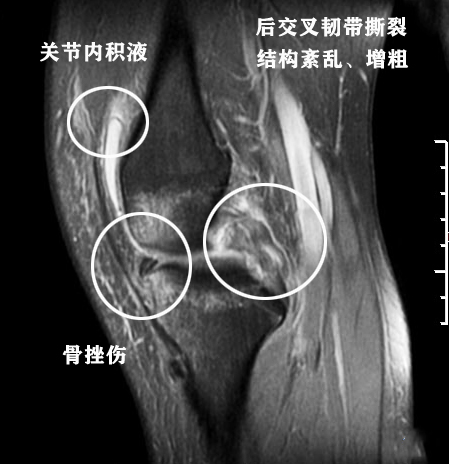

第三,前交叉韧带损伤可能。检查所见内提示前交叉韧带内线性高亮信号影,这个我要跟大家详细说明一下,前交叉韧带是分为前内与后外两束的,在两束之间会有脂肪间隙,这个间隙在核磁上看起来就是线性的高亮信号影。那么针对这个患者可能有两种情况,一是这个患者没有外伤,核磁所见是正常的,是由于阅片医生缺乏经验给与的前交叉韧带损伤描述;另外一种是这个患者受过外伤,前交叉韧带有损伤,但是不重。严重的前交叉韧带撕裂会提示韧带走形结构紊乱,水肿等其他词汇,下图就是一个严重的后交叉韧带撕裂的孩子的核磁影像。